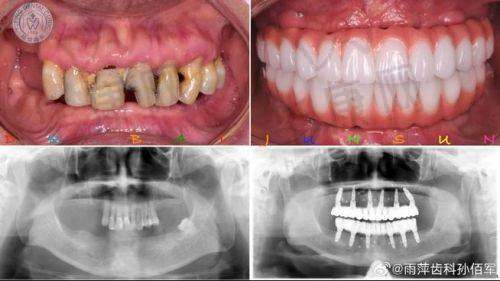

湖南湘西口腔医院何春秀全口即刻种植牙之诊疗成效

经过一段时间的修复,我的全口即刻种植牙成效非常显著。现在我可以像正常人一样吃饭、说话了,再也不用担心牙齿缺失带来的尴尬和不便。牙齿变得整齐美观,让我的笑容也更加自信了。而且,种植的牙齿稳定性特别强,咀嚼功能也修复得良好,我可以尽情享受美食了。这种改变真的让我非常惊喜,也非常感激何春秀医生和湖南湘西口腔医院的医护人员。